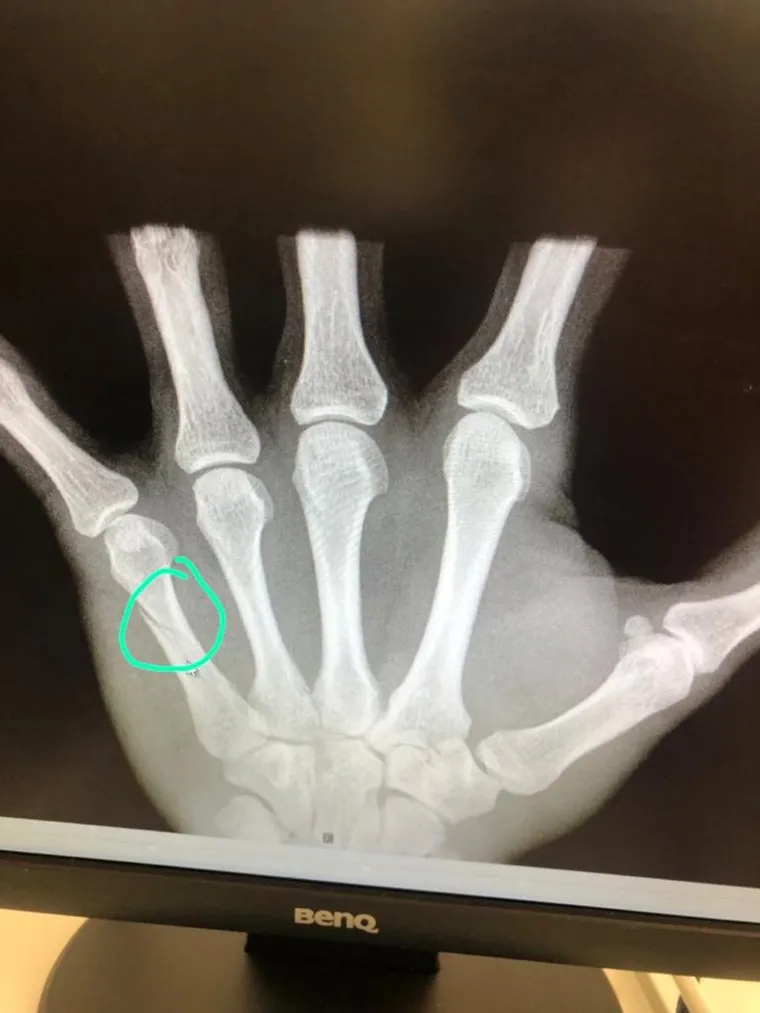

«Сегодня на тренировке при спуске по трассе, на которой проходит чемпионат мира по лыжным гонкам, упал Денис Спицов. У него диагностирован перелом пятой пястной кости левой руки», — сообщается в пресс-релизе на сайте Федерации лыжных гонок России.

Травма не позволит Спицову продолжить участие в чемпионате мира, который сейчас проходит в Германии. В ближайшее время спортсмен вернется на лечение в Россию. Восстановление займет до шести недель.

Лыжник получил перелом костей руки